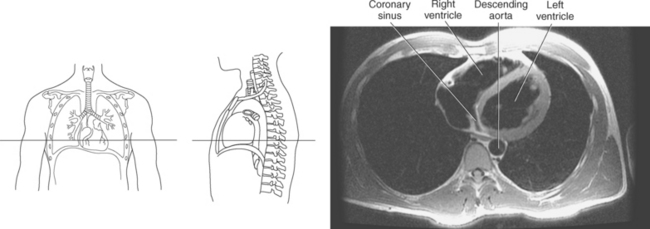

The right atrium forms the right border of the heart and receives deoxygenated blood from the body via the superior and inferior venae cavae and from the coronary sinus and cardiac veins that drain the myocardium. A small muscular embryonic appendage, the right auricle, projects upward and toward the left from the right atrium, covering the root of the aorta (Figure 6.40). The right ventricle lies on the diaphragm and comprises the largest portion of the anterior surface of the heart. It receives deoxygenated blood from the right atrium and forces it into the pulmonary trunk for conveyance to the lungs. Projecting off the inferior surface of the ventricular walls are conical-shaped projections of cardiac muscle called papillary muscles that anchor the cusps of the tricuspid valve to the right ventricle (Figure 6.39). The left atrium lies posterior to the right atrium and is the most posterior surface of the heart. It also has an embryonic appendage, the left auricle, that projects to the left of the pulmonary trunk over the superior surface of the heart. The left atrium receives oxygenated blood directly from the lungs via the four pulmonary veins (two on each side). The left ventricle forms the apex, left border, and most of the inferior surface of the heart. It receives oxygenated blood from the left atrium and pumps it into the aorta for distribution throughout the systemic circuit. The myocardium of the left ventricle is normally three times thicker than that of the right ventricle, reflecting the force necessary to pump blood to the distant sites of the systemic circulation (Figures 6.41 through 6.52). Two papillary muscles project from the ventricular walls to anchor the bicuspid valve to the ventricle (Figures 6.39 and 6.47).

Figure 6.43 Axial, T1-weighted MR scan of left atrium.

Key: RV, Right ventricle; LV, left ventricle; LA, left atrium; RA, right atrium.